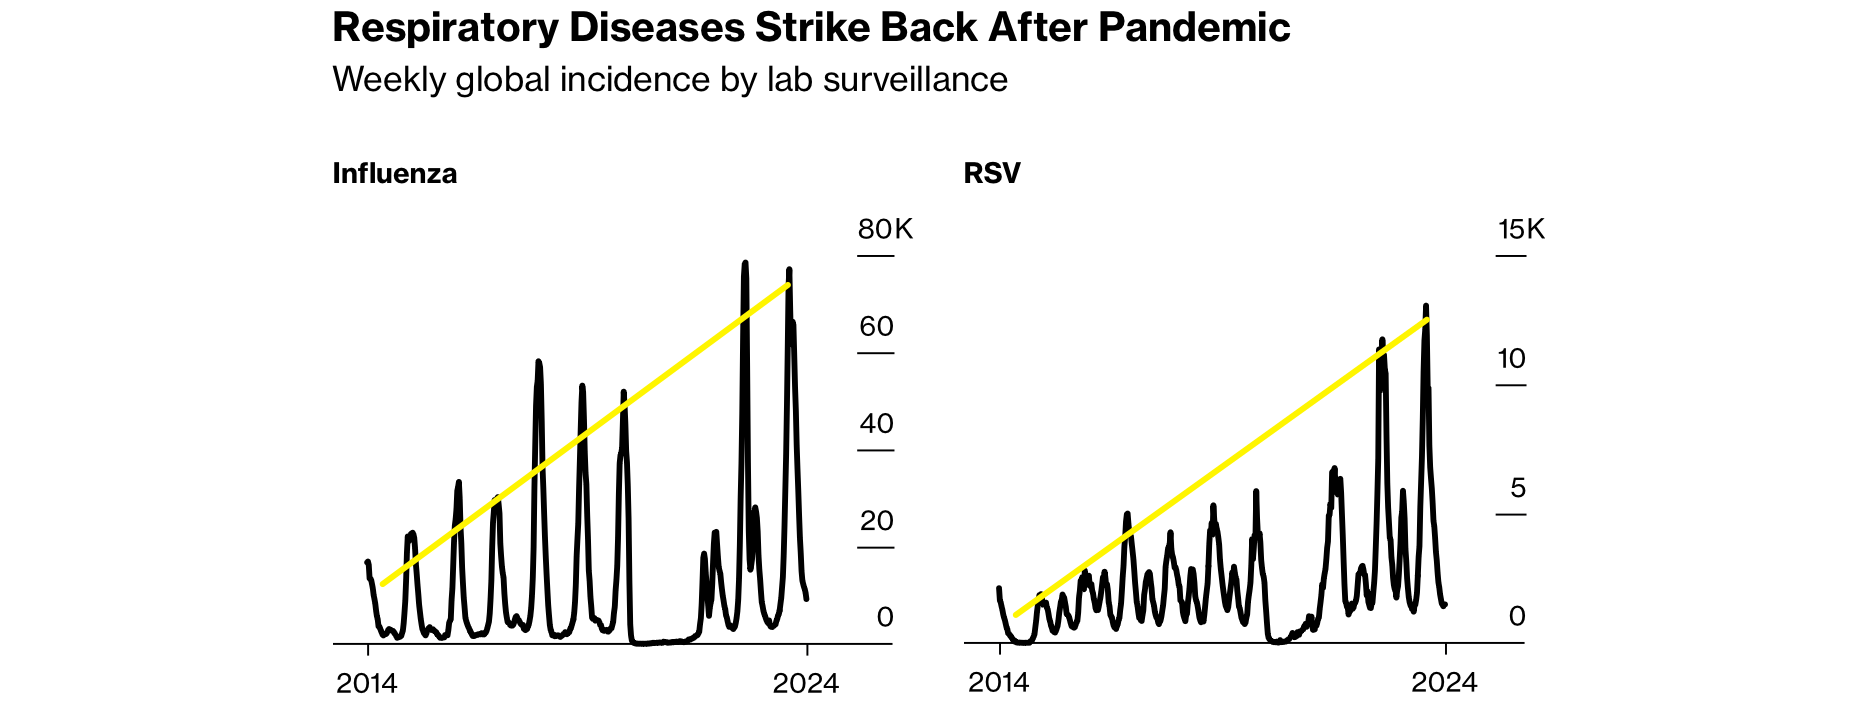

💉 Bloomberg reported another baffling scientific mystery Friday in a story headlined, “Yes, Everyone Really Is Sick a Lot More Often After Covid.” Another conspiracy theory is almost now confirmed as conspiracy fact. The article included the strongest hints yet at the truth. The truth is out there.

Well, not everywhere. Bloomberg’s research, compiled from over 60 organizations and public health agencies, revealed that 44 countries and territories have each reported at least one disease resurgence at least ten times worse than pre-pandemic baselines. The prosperous germs include viruses, bacteria, fungi, rare ones, common ones, across the whole spectrum of infection.

For only a few examples, flu in the U.S. is up +40%. Whooping cough has surged over 45 times in China, just in 2024’s first four months. In Australia, RSV cases have nearly doubled from last year. It’s a multi-pandemic worse than covid.

Argentina is weathering its worst dengue outbreak ever. Japan is managing a mysterious surge of Strep A. Measles is making a comeback in twenty American states, in the UK, and in Europe. Globally, 7.5 million people were newly diagnosed with tuberculosis in 2022 — the worst year since the WHO began tracking TB in the mid-1990s.

Case after case, disease after disease, country after country, the numbers keep creeping up. And it’s a baffling mystery.

They got so close. Repeatedly, Bloomberg’s experts noticed that people’s immune systems seem somehow to be damaged. But in their vacuum of good ideas, the confused experts are chalking it up, maybe, partly, to lockdown-induced immunity debt. The “bubble boy” problem:

Modern medicine is off the map, flailing, for once speechless and diagnosis-less. The WHO’s chief scientist, Jeremy Farrar, shrugged and said, “we are in a new territory here.” But intentionally or unintentionally, Bloomberg seeded the article with suggestive kernels of truth. For example, the perplexed experts noted that mysteriously spiking excess deaths are strangely, bafflingly clustered in the most highly jabbed countries, the ones that “did the best job” during the pandemic:

Like the things going on, the article’s efforts to explain the trend were also complicated. It considered a long menu of possibilities, from immunity debt to climate change to racism to vaccine hesitancy. But none of those lackluster ideas were satisfactory. None could explain the full breadth of the increase, since even illnesses without vaccines (like fungal infections) are also rising fast.